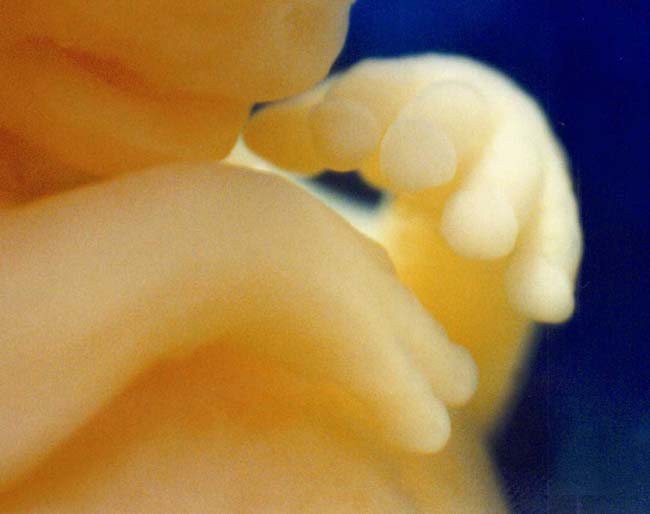

12 week ultrasound

She was 12 weeks pregnant, though she had taken birth control pills as directed. “I feel pretty messed up,” she said after seeing the image. “It’s different, just knowing. My husband told me not to look. This changes my feelings, but I’m sticking by it. Damn it, $650, I’m sticking by it.”